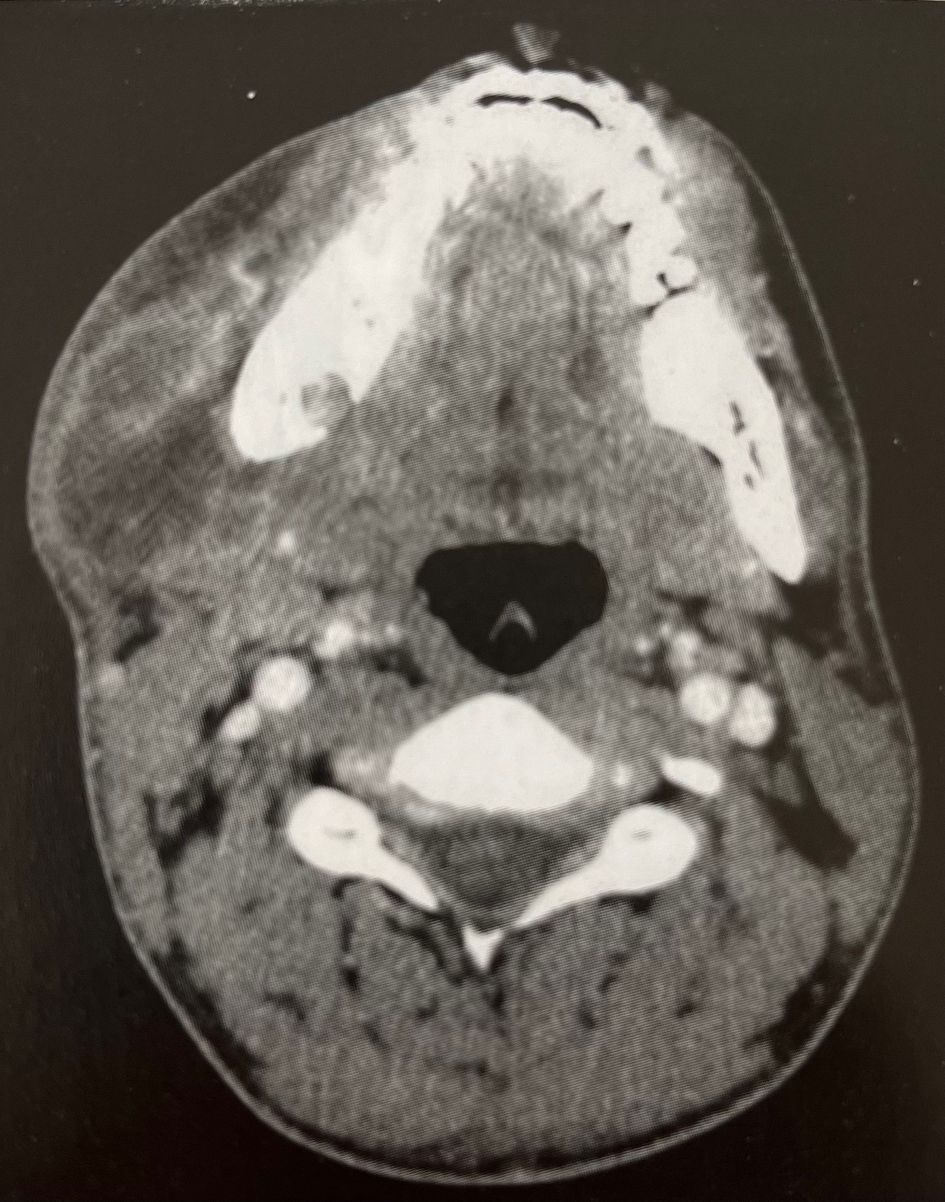

Annexe 1

Il consulte ce jour aux urgences pour une tuméfaction évoluant depuis 6 jours. Vous avez réalisé des examens complémentaires que vous trouverez en annexe.